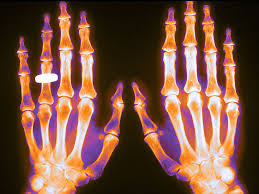

Cribado para reducir las fracturas por fragilidad: nuevos ensayos, aún ineficaces

Este Therapeutics Letters resume los resultados de los programas de detección intensivos destinados a prevenir fracturas en adultos mayores. Como herramientas de detección, la DMO y el FRAX no predicen de manera confiable quién sufrirá fracturas por fragilidad. La edad, los antecedentes de caídas y el uso de ciertos medicamentos predicen mucho mejor el riesgo. 28 de febrero de 2024